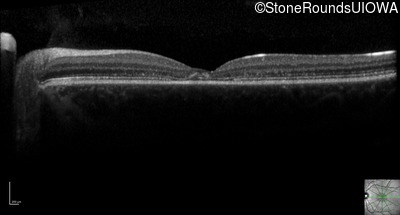

Optical Coherence Tomography - Right - 20/40 -2

Exemplar / OCT Stack